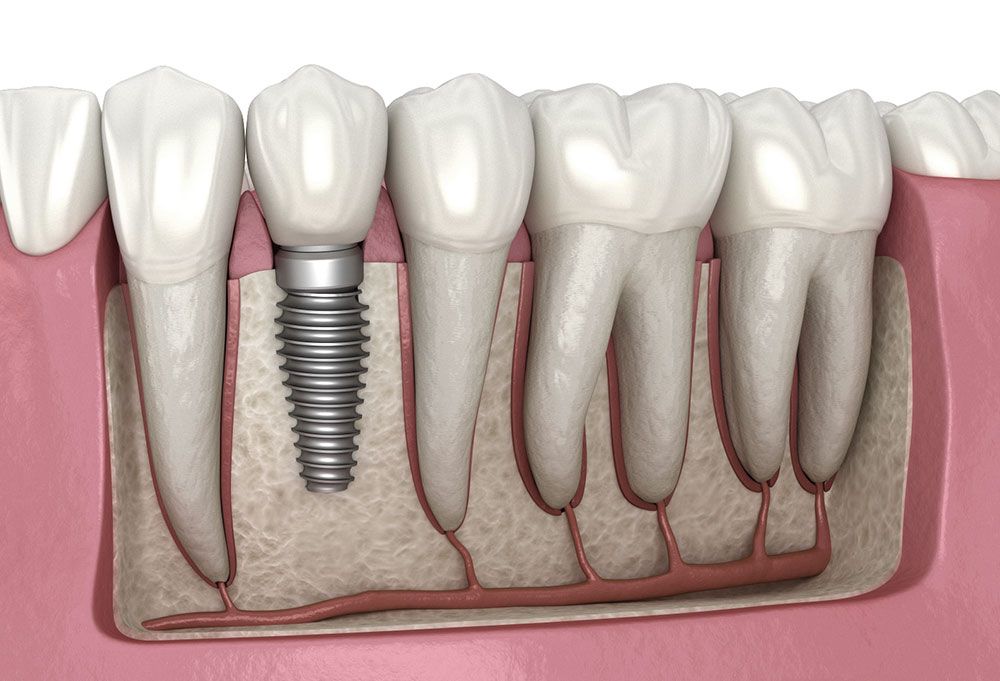

Dental Implant

A lifetime permanent solution

Bicon USA Trained

Certified in the American Bicon implant system — precision short implants

IAT Implant System - Japan

IAT Japanese implant system — advanced precision engineering

Osstem Implant - South Korea

Osstem South Korean implant system — world-renowned reliability